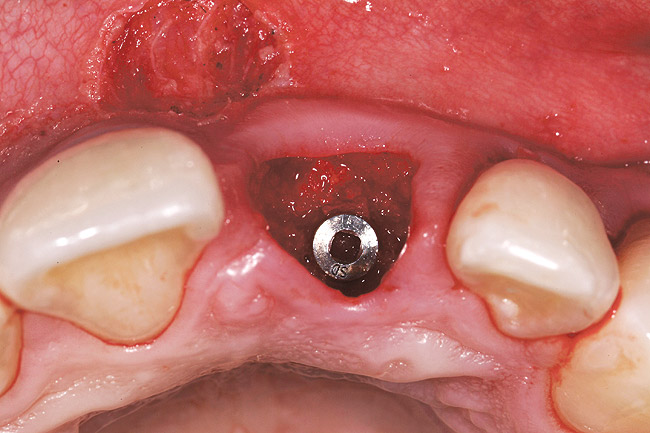

The patient opted for the third option. After administration of an appropriate local anesthetic, a frenectomy was performed using a Nd:Yag laser. This would allow for the loosening of the facial tissues and the coronal repositioning of the pouch at the termination of the procedure. After the frenectomy, the left central incisor was removed by an atraumatic technique preserving the soft tissue emergence profile (Figure 23). Debridement of the extraction socket preceded atraumatic site preparation techniques. A 3.5-mm diameter by 13-mm tapered implant (Prima Connect, Keystone Dental, www.keystonedental.com) was placed to the appropriate depth measurements planned.38,39

Once the implant was seated, the cover screw was placed, and the facial defect at the buccal aspect of the implant was corrected using mineralized, large-particle cancellous chips (Lifenet, www.lifenet.org) and a solution of PRP, forming a graft/PRP gel complex. The graft complex was heavily condensed into the void present, to the level of the facial aspect of the polished collar on the implant (Figure 24).

After placement of the graft complex, a titanium abutment with a 1-mm collar (Quick abutment, Keystone Dental) was seated and hand-tightened (Figure 25). Retrofitting of the natural tooth shell preserving the pre-existing contact point relationships and line-angle positioning was accomplished from a pretreatment incisal edge registration. The final provisional restoration can be seen in Figure 26.

Figure 24  Case Three Minimally invasive bone grafting, occlusal view.

Figure 24

Figure 25  Case Three Titanium abutment seated

Figure 25